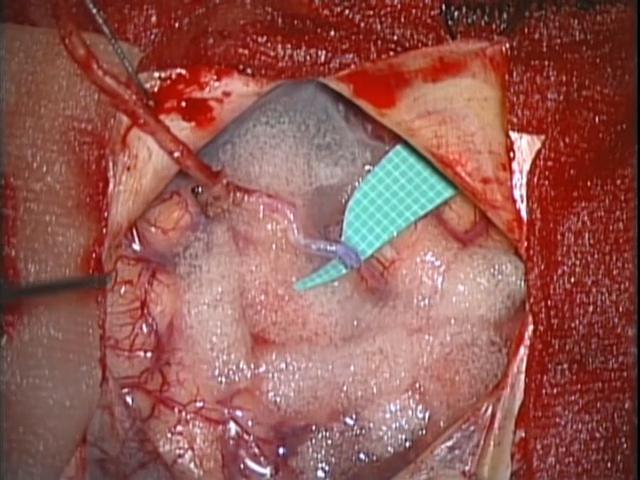

- くも膜下出血

急性期治療の重要なポイントは、破裂した動脈瘤の再破裂をできるだけ早く防止することです。再破裂は生命予後を著しく悪化させるため、発症後早期に治療をするのが一般的です。急性期手術としては開頭クリッピング術とコイル塞栓術の2つの方法があります。開頭クリッピング術は、全身麻酔で頭皮を切開し、頭蓋骨の一部を開けて顕微鏡下で動脈瘤に到達し、クリップで動脈瘤の根元をはさみ血流を遮断する手術です。これにより再破裂を防ぎます。手術は直接血管にアクセスするため確実な処置が可能です。コイル塞栓術は足の付け根の動脈からカテーテルを挿入し、脳内の破裂動脈瘤内に細いマイクロカテーテルを通してプラチナ製のコイルを詰める方法です。これにより動脈瘤を閉塞し再破裂を防止します。侵襲が少なく入院期間が短い場合も多いですが、動脈瘤の形状や場所により適応が異なります。

術前

術後